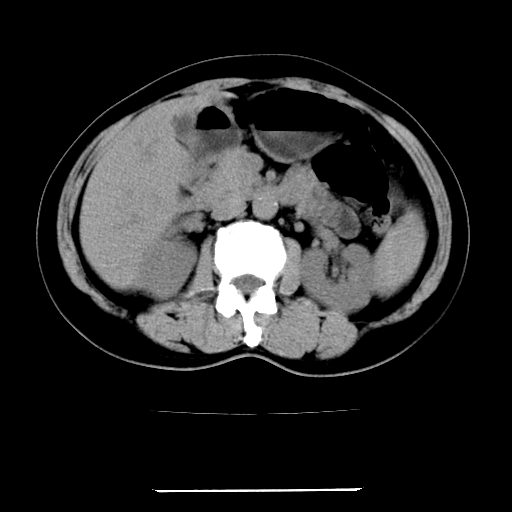

女,67岁,上腹部疼痛一周伴皮肤黄染,无发热。

左叶肝内胆管结石,并远端肝内胆管扩张。

考虑:肝内胆管结石继发肝内胆管扩张,右肾旋转不良。

肝内外胆管结石并肝内胆管扩张。

肝内外胆管扩张,左叶胆管内结石

1、肝门高密度影下层面和胰头层面可见轻度胆管扩张,而静脉和延迟期均未见扫描完胰头,不能完全排除胰头占位。2、肝门部高密度影,考虑钙化或结石。